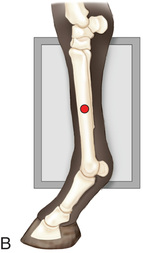

| Metacarpal/metatarsal cannon bone (M3) | Dorsoproximal-palmarodistal (DPr-PaDi) | Dorsopalmar (DP) |

| Lateromedial (LM) | Lateral (L) | |

1. Safety is a priority when taking radiographs. To keep personnel away from the central ray when the metacarpus of large animals is being radiographed, you should:

c. Use a cassette holder with a clamp and long handle